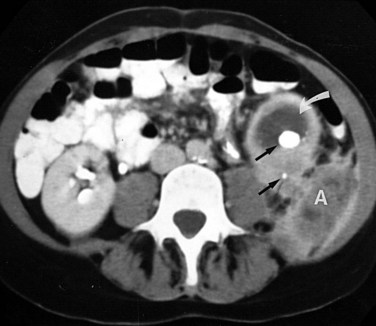

Ultrasonography usually demonstrates strong focal echoes suggesting the presence of intraparenchymal gas (Brenbridge et al, 1979; Conrad et al, 1979). CT is the imaging procedure of choice in defining the extent of the emphysematous process and guiding management (Figs. 10-23 and 10-24). An absence of fluid in CT images or the presence of streaky or mottled gas with or without bubbly and loculated gas appears to be associated with rapid destruction of renal parenchyma and a 50% to 60% mortality rate (Wan et al, 1996; Best et al, 1999). The presence of renal or perirenal fluid, the presence of bubbly or loculated gas or gas in the collecting system, and the absence of streaky or mottled gas patterns is associated with a less than 20% mortality rate. Obstruction is demonstrated in approximately 25% of the cases. A nuclear renal scan should be performed to assess the degree of renal function impairment in the involved kidney and the status of the contralateral kidney.

The diagnosis is established radiographically. Tissue gas that is distributed in the parenchyma may appear on abdominal radiographs as mottled gas shadows over the involved kidney (Fig. 10–22). This finding is often mistaken for bowel gas. A crescentic collection of gas over the upper pole of the kidney is more distinctive. As the infection progresses, gas extends to the perinephric space and retroperitoneum. This distribution of gas should not be confused with cases of emphysematous pyelitis in which air is in the collecting system of the kidney. Emphysematous pyelitis is secondary to a gas-forming bacterial UTI, often occurs in nondiabetic patients, is less serious, and usually responds to antimicrobial therapy.

Figure 10–22 Emphysematous pyelonephritis; plain film. Extensive perinephric (long arrows) and intraparenchymal (short arrows) gas secondary to acute bacterial pyelonephritis.

(From Schaeffer AJ. Urinary tract infections. In: Gillenwater JY et al, editors. Adult and pediatric urology. Philadelphia: Lippincott William & Wilkins; 2002. p. 211–72.)